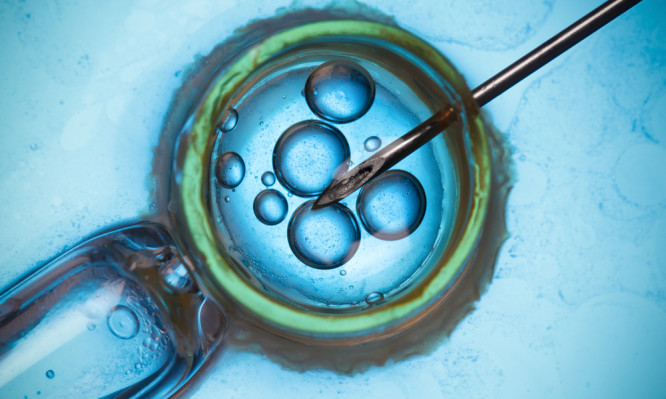

Μονάδα Γονιμότητας & Εξωσωματικής Γονιμοποίησης ΡΕΑ: Το όνειρό σας γίνεται πραγματικότητα!

Η Κλινική ΡΕΑ, έχοντας ξεχωρίσει για τις υψηλού επιπέδου Μαιευτικές και Γυναικολογικές Υπηρεσίες της, δημιούργησε μια σύγχρονη Μονάδα Γονιμότητας – Εξωσωματικής Γονιμοποίησης, με στόχο τη διερεύνηση, τη σωστή διάγνωση και την αποτελεσματική αντιμετώπιση της υπογονιμότητας στα σύγχρονα ζευγάρια....